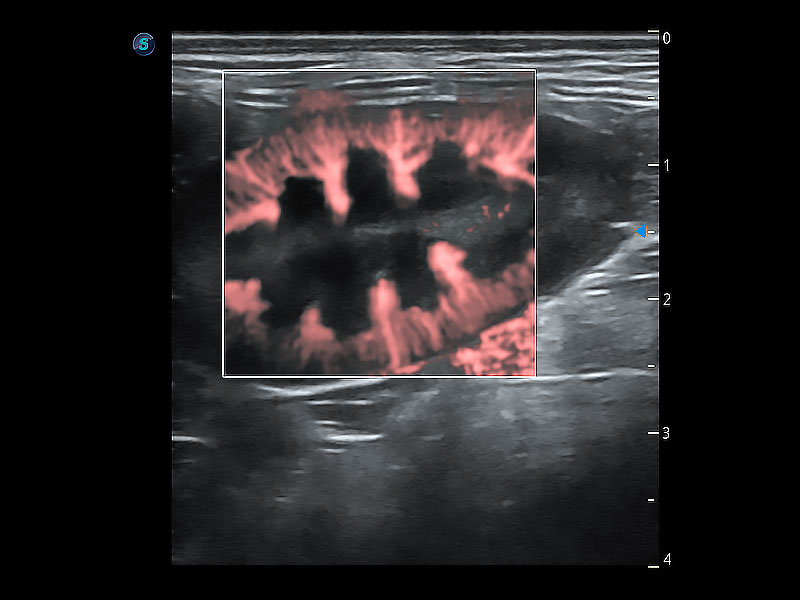

操作简便,无需高频度外力作用即可真实反映组织的形变,快速评估肿瘤良恶性。

非线性融合造影成像充分利用谐波和基波信号,为难以观察的血流进行增强显像。可用于线阵、凸阵、微凸阵、相控阵探头。